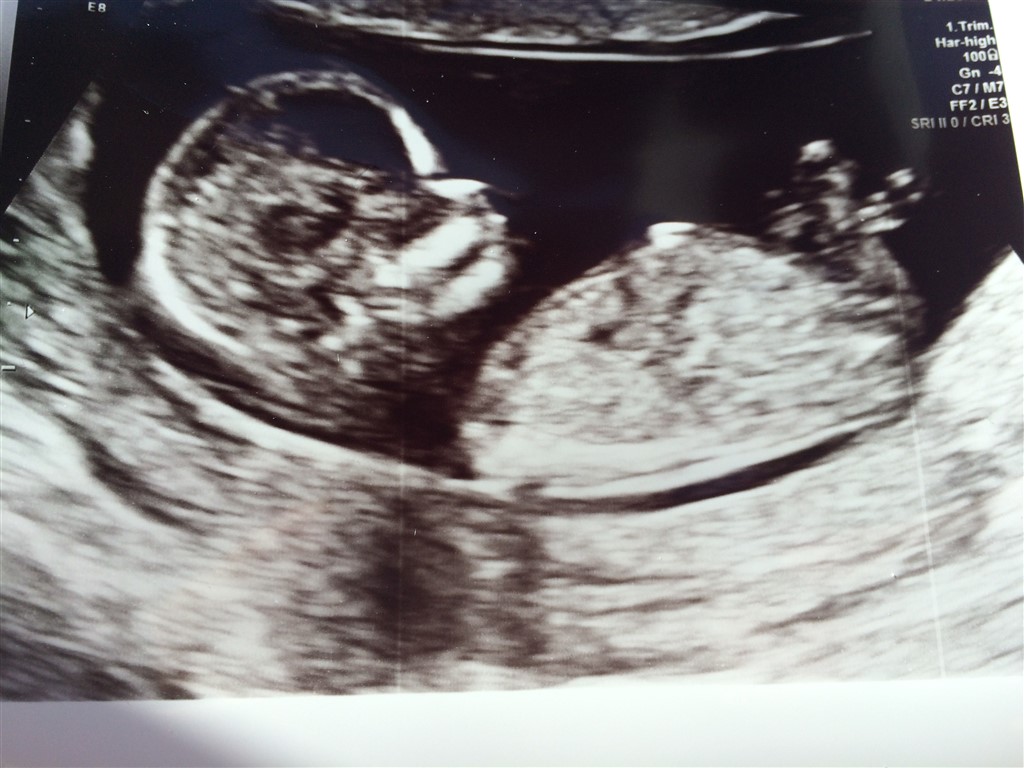

Vi var igår til nf, og alt var godt. Er 13+1 idag. Nu er jeg selvfølgelig mega spændt på at finde ud af hvilket køn der gemmer sig i maven.

Er der nogen der er mega seje til at gætte køn?